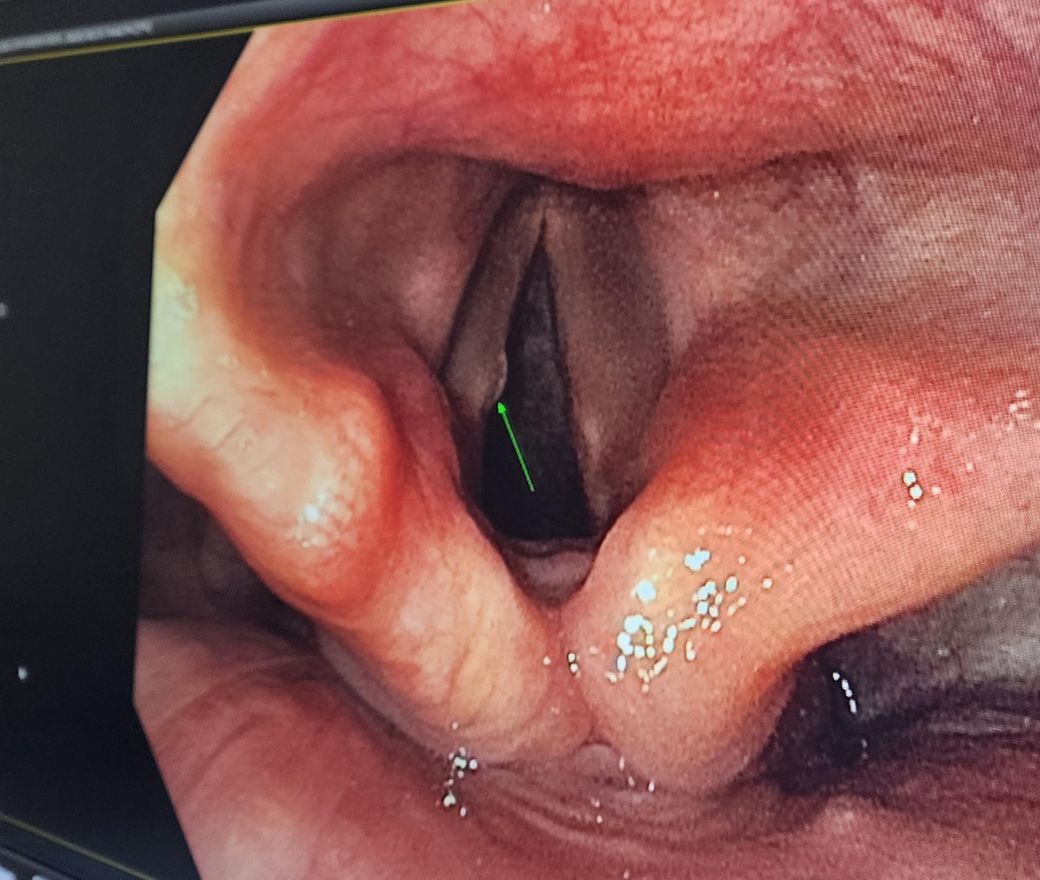

성대결절인지? 잘모르겠습니다 병명

말씀하시는 성대결절로 인한 증상으로 보이지는 않습니다.

성대결절의 경우 생활습관변화, 주사치료등으로 치료가 가능합니다.

안녕하세요. 최규은 내과 전문의입니다.

사진상으로는 성대결절이 의심됩니다. 가까운 이비인후과에 방문하여 진료를 보시는게 좋겠습니다. 감사합니다.